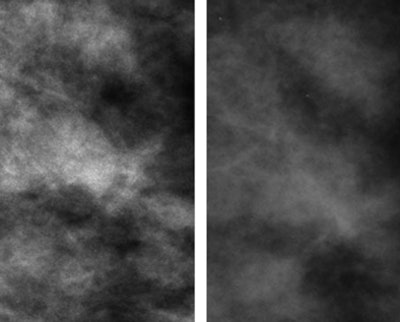

| Craniocaudal mammographic views of dense left breast in 52-year-old-woman. Full digital mammogram obtained by using Senographe system (above, left) and close-up view (below, left) of area outlined (in rectangle), as compared with full film-screen mammogram of same breast (above, right) and close-up view (below, right) of area outlined (in rectangle), reveal how improved contrast in dense part of the breast depicted on the digital mammogram enables visualization of the cancer, an invasive ductal carcinoma, on the digital image but not on the film-screen image. The lesion was not visible on either the mediolateral oblique film-screen or digital mammograms. |